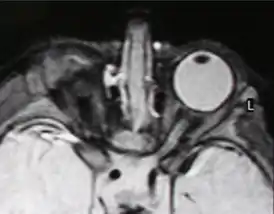

![]() Правосторонняя анофтальмия (МРТ-изображение) | |